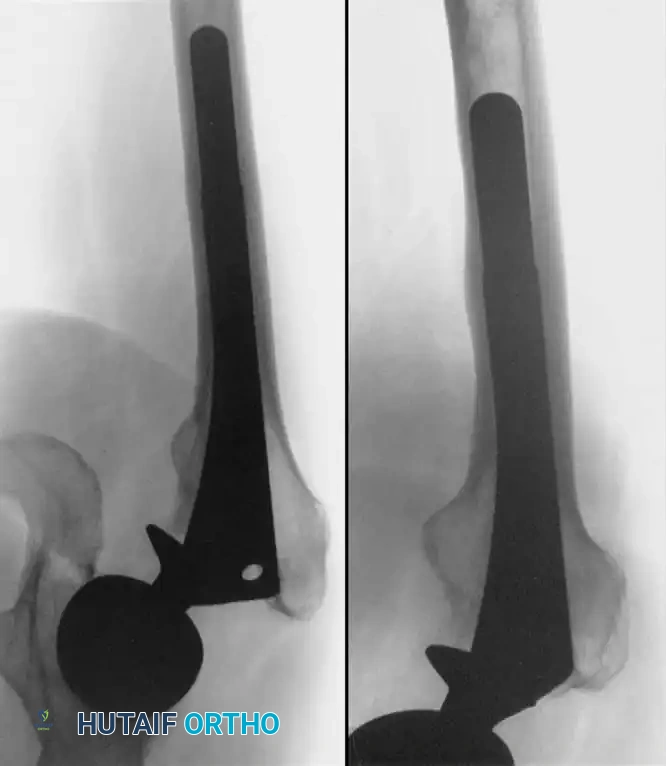

Associated Surgical & Radiographic Imaging